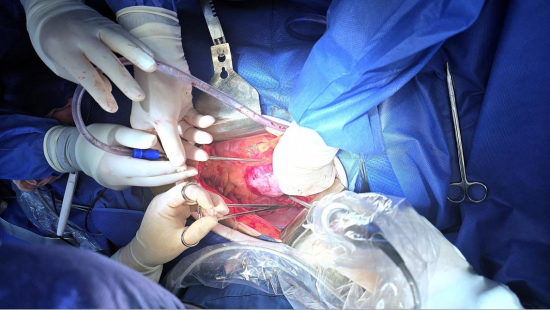

历经数小时紧张而精细的操作,手术在两位主刀专家的精准掌控下稳步推进。当最后一针缝合完成,不仅意味着肿瘤被成功切除,更标志着一场高难度的生命护航顺利抵岸。

李广恩教授表示:“每一例复杂腹膜后肿瘤手术,都是对团队技术与意志的双重考验。我们成立专家工作室,正是为了汇聚顶尖技术,结合本地团队的深厚经验与不懈努力,为黑龙江省乃至东北地区的复杂腹膜后肿瘤患者提供最规范、最前沿、最有效的治疗。患者的信任,始终激励我们勇闯禁区、不懈钻研。”